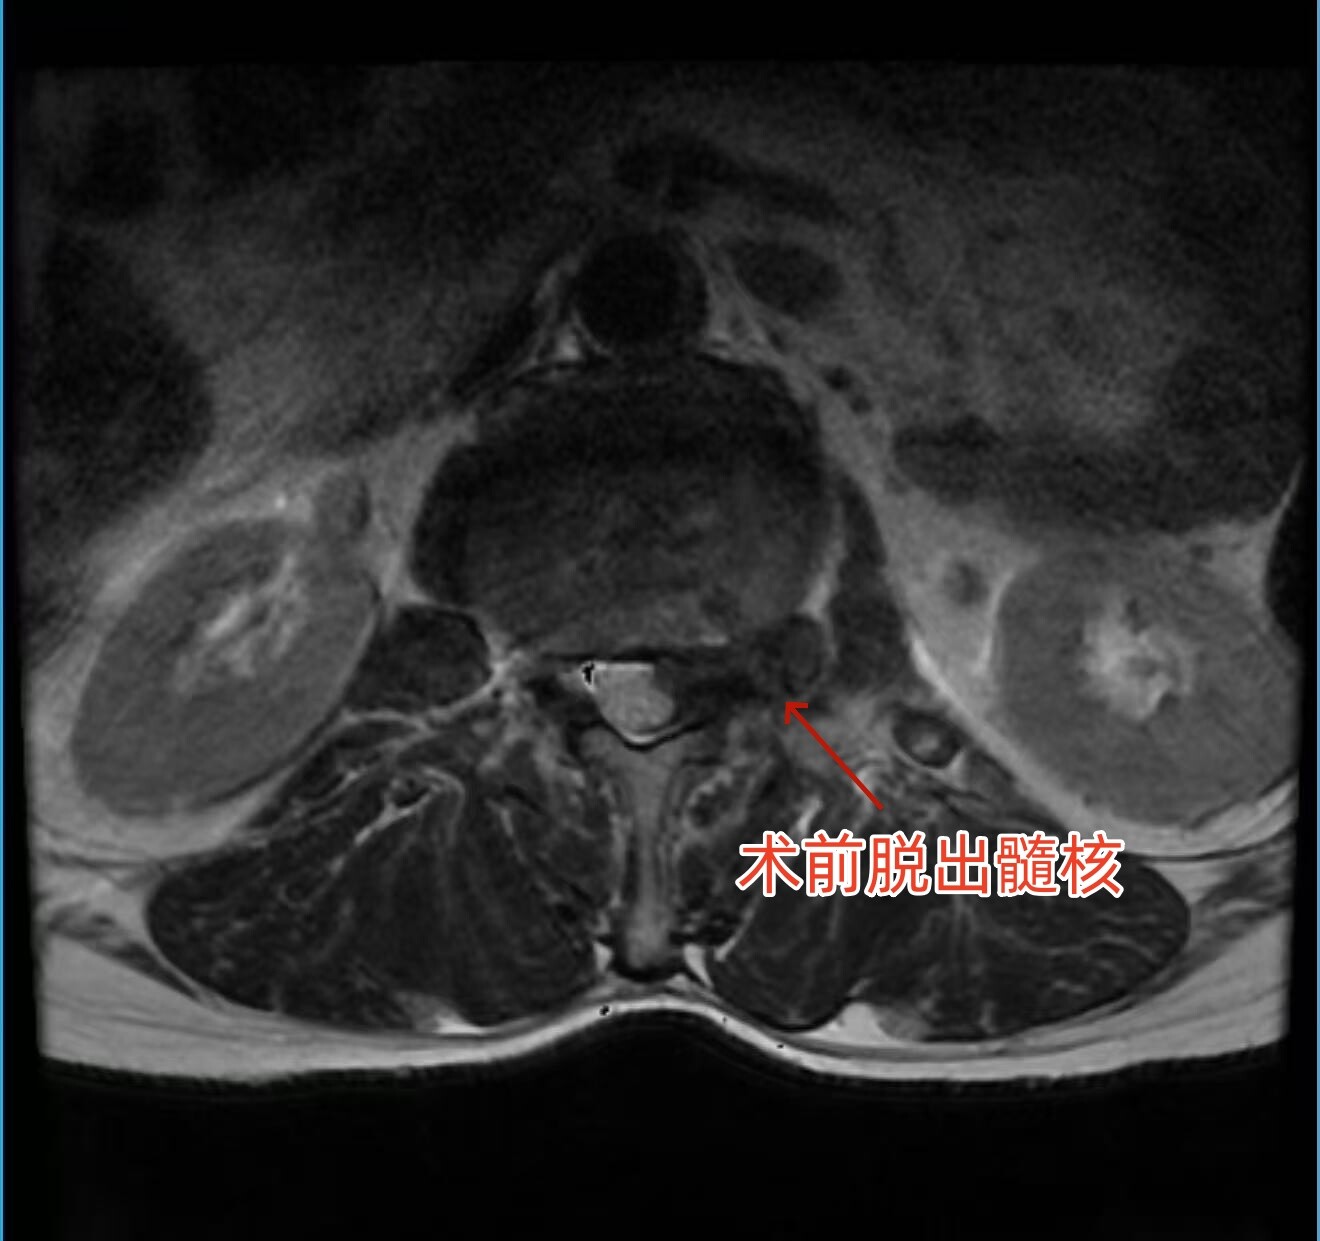

患者慕名来到永兴县人民医院骨二科。接诊后,医生团队通过详细查体和腰椎MRI检查,明确诊断为“腰椎间盘突出症(腰2/3、脱出型)”。检查显示,脱出的髓核组织不仅存在于椎管内,还延伸至椎间孔及椎间孔外,严重压迫左侧腰2出口神经根,这正是患者剧烈疼痛、无法行走的根本原因。

术中,在高清椎间孔镜辅助下,医生精准定位病变节段,小心避开神经根及周围重要组织,逐步剥离并摘除压迫神经的髓核组织。整个手术过程精准、微创、出血少,历时仅1小时,术后伤口仅缝一针。

术后,患者左侧大腿前方的剧烈疼痛完全消失,肢体活动恢复正常。术后第二天,患者即可下地行走自如,精神状态明显好转。复查腰椎MRI显示,压迫神经根的髓核已被彻底摘除,神经根压迫完全解除。